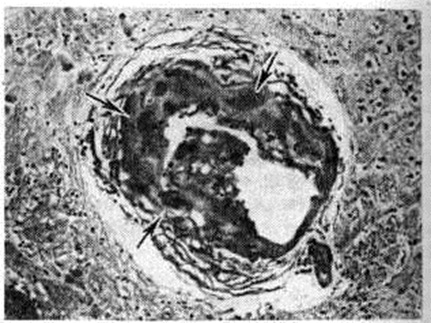

Рис. 3.

Микропрепарат ткани головного мозга с аневризматическим расширением мелкой артерии (стрелками указана микроаневризма); окраска гематоксилин-эозином; × 200.

Геморрагический инсульт, как правило, возникает при заболеваниях, протекающих с повышенным артериальное давление. Это обусловлено тем, что сосудистые кризы (смотри полный свод знаний), характерные для гипертонической болезни (смотри полный свод знаний) и артериальной гипертензии (смотри полный свод знаний Гипертензия артериальная), приводят к морфологический изменениям стенок внутримозговых сосудов с нарушением их проницаемости — плазматическому пропитыванию (рисунок 1), некрозам (рисунок 2), образованию микроаневризм (рисунок 3) и их разрывам. Разрыв врождённых артериальных и артериовенозных аневризм может протекать на фоне нормального давления. Преимущественная локализация и характер геморрагий определяются особенностями ангиоархитектоники различных отделов мозга. При гипертонической болезни наиболее тяжёлым изменениям подвергаются сосуды подкорковых узлов и зрительного бугра. Это объясняется отхождением глубоких ветвей под прямым углом от средней мозговой артерии, являющейся продолжением внутренней сонной артерии, и незначительным числом анастомозов сосудов в этой области. В связи с этим на вскрытии кровоизлияния наиболее часто (40%) обнаруживаются в подкорковых узлах с распространением в прилежащее белое вещество (так называемый латеральные кровоизлияния, то есть расположенные латерально от внутренней капсулы, рисунок 4). Второе место по частоте (16%) занимают обширные кровоизлияния, разрушающие подкорковые узлы, внутреннюю капсулу, зрительный бугор (так называемый смешанные кровоизлияния — рисунок 5). Кровоизлияния в зрительный бугор (так называемый медиальные — рисунок 6) составляют 10%, в мозжечок — 6—10%, в мост мозга — 5% от общего числа внутримозговых геморрагий. Кровоизлияния только в белое вещество полушарий мозга встречаются крайне редко. Подразделение полушарных кровоизлияний на латеральные, медиальные и смешанные имеет особое значение в связи с хирургическим лечением геморрагического Инсульт.